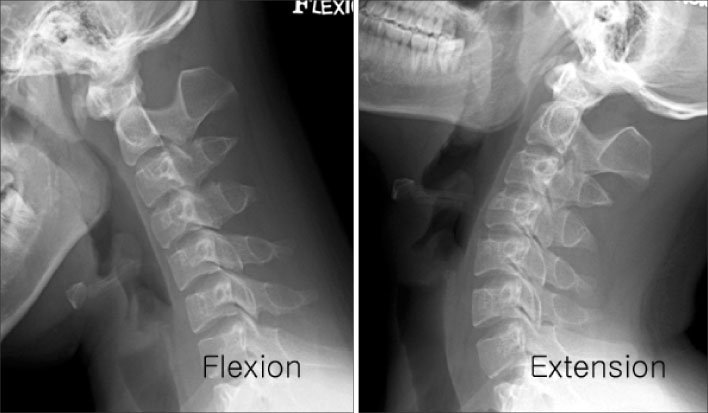

X-rays of the cervical spine taken while the patient bends their neck forward (flexion) and backward (extension).

| To assess the range of motion and stability of the cervical spine, useful in diagnosing conditions like whiplash, ligament injuries, or instability. |